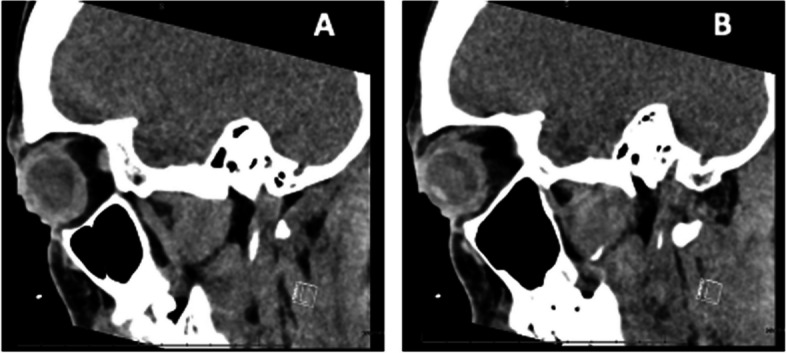

Conclusion: Computed tomography (CT) of the face and sinuses showed bilateral circumferential globe thickening. IGRA was positive. All other rheumatologic and infectious workups were negative, including HIV, ACE, ANA, ANCA, CRP, anti-scleroderma antibody and HCV. The patient was treated with intravenous methylprednisolone and seven months of rifampin, isoniazid, pyrazinamide, and ethambutol. This workup shows the rare bilateral corneal involvement of ocular tuberculosis.